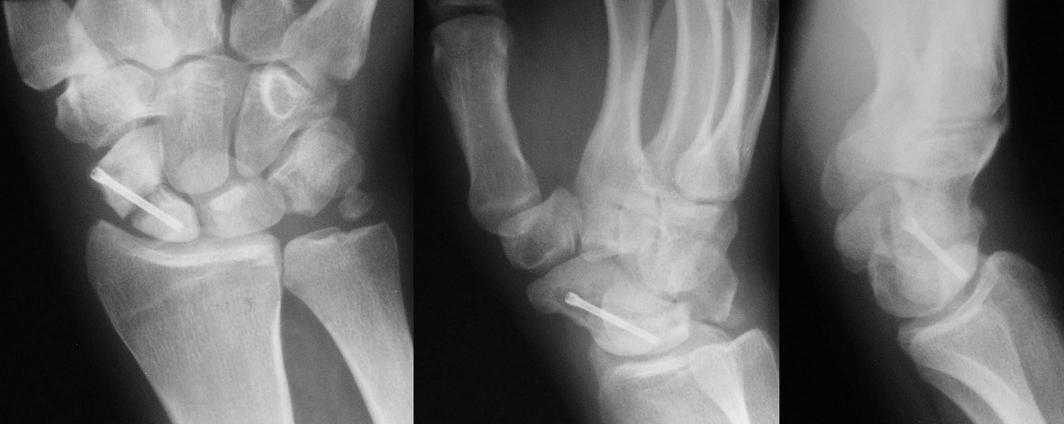

I am not sure if the differential of a nonunion vs. pseudoarthrosis means much in this context. The distal pole of the screw has a lucency, so the

nonunion is most likely unstable and moving. It needs revision. The radial styloid does not have evidence of DJD, so I do not think it needs to be resected. The surgery will probably require an open revision, removal of necrotic bone and soft tissue interposition, and would benefit from some

Такое ощущение, что имеющееся состояние ещё не является необратимым (отсутствие склероза отломков на уровне перелома) и обусловлено исключительно нестабильностью (сам винт оказался слабоват или чрезмерные нагрузки привели к срыву фиксации - пациент, заметьте, мотоциклист!)

Почему-то хочется верить, что можно добиться сращения, если вернуть кости стабильность путём компрессионного остеосинтеза более мощным винтом без открытого вмешательства на компрометированной зоне и защитить фиксацию строгим соблюдением режима. Я сильно ошибаюсь?

Ув. Данил! По моему мнению все-таки ложный сустав -склероз отломков (приложение), 5 мес, диастаз. Для подтверждения можно выполнить КТ кистевого сустава (формирование замыкательной пластинки, склероз концов отломков и т.д.,), а так же по КТ можно выявить сохраняется ли подвывих каких-либо костей запястья или нет. При наличии ложного сустава целесообразно будет удалить винт,обработать концы отломков, разрушив замыкательные пластинки и выполнить остеосинтез ладьевидной кости винтом с костной аутопластикой зоны псевдоартроза (либо гидроксиаппатитом...) Гипс 1,5 мес мин. Снимков найти сейчас не получилось. позже дошлю.